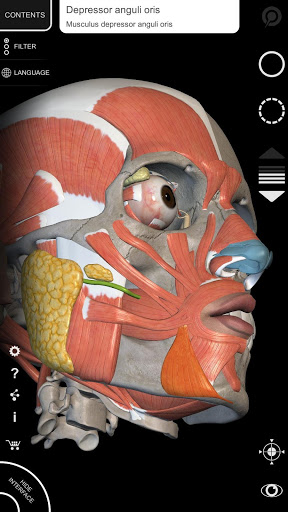

"Anatomy 3D Atlas" memungkinkan Anda mempelajari anatomi manusia dengan cara yang mudah dan interaktif.

Melalui antarmuka yang sederhana dan intuitif, Anda dapat mengamati setiap struktur anatomi dari sudut mana pun.

Model 3D anatomi sangat terperinci dan memiliki tekstur hingga resolusi 4k.

Pembagian berdasarkan wilayah dan tampilan yang telah ditetapkan sebelumnya memudahkan pengamatan dan studi bagian tunggal atau kelompok sistem dan hubungan antara organ yang berbeda.

MODEL ANATOMI 3D

• Sistem muskuloskeletal

saraf • Sistem pernapasan • Sistem pencernaan • Sistem urogenital (pria dan wanita) • Sistem endokrin • Sistem limfatik • Sistem mata dan telinga FITUR • Antarmuka yang sederhana dan intuitif • Putar dan perbesar setiap model dalam ruang 3D • Opsi untuk menyembunyikan atau mengisolasi satu atau beberapa model yang dipilih • Filter untuk menyembunyikan atau menampilkan setiap sistem • Fungsi pencarian untuk menemukan setiap bagian anatomi dengan mudah • Fungsi penanda untuk menyimpan tampilan khusus • Rotasi cerdas yang menggerakkan pusat rotasi secara otomatis • Fungsi transparansi • Visualisasi otot melalui tingkat lapisan dari yang superfisial hingga yang terdalam • Dengan memilih model atau pin, istilah anatomi terkait akan muncul • Deskripsi otot: asal, • Tampilkan/ Sembunyikan antarmuka UI (sangat berguna dengan layar kecil) MULTIBAHASA • Istilah anatomi dan antarmuka pengguna tersedia dalam 11 bahasa: Latin, Inggris, Prancis, Jerman, Italia, Portugis, Turki, Rusia, Spanyol, Mandarin, Jepang, dan Korea • Istilah anatomi dapat ditampilkan dalam dua bahasa secara bersamaan PERSYARATAN SISTEM • Android 8.0 atau yang lebih baru, perangkat dengan RAM minimal 3GB Reversi